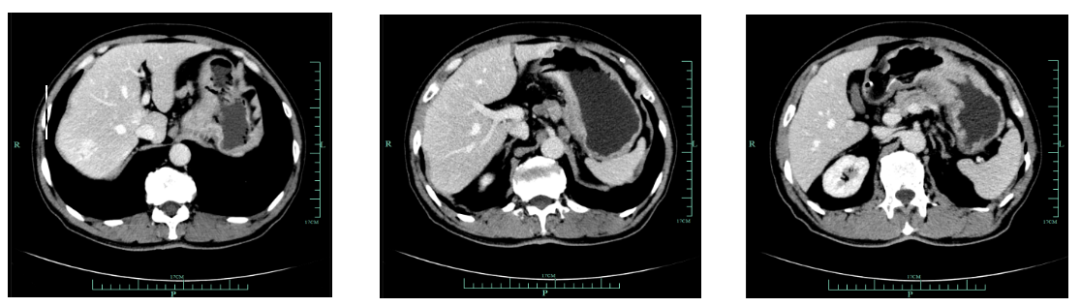

现病史:1月余前出现吞咽哽噎,无饮水呛咳,偶感腹胀腹痛,无恶心呕吐等不适,至外院就诊,上腹部增强CT(2018-12-14)提示:胃小弯及贲门壁异常,提示胃癌。胃周多发肿大淋巴结转移考虑。

既往史(续):全腹部CT平扫+增强提示胃贲门部及体部胃壁增厚,结合临床考虑胃癌伴胃周及腹膜后多发淋巴结转移;肝脏多发血管瘤。